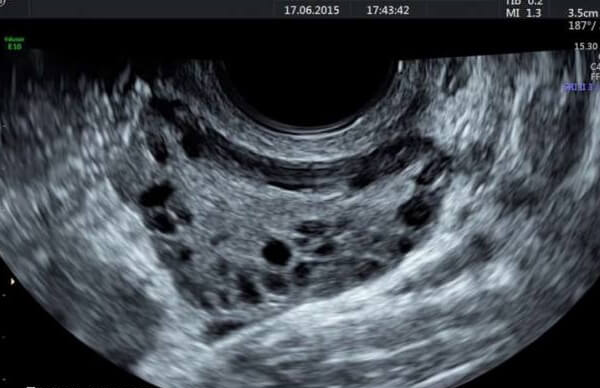

多囊卵巢综合征被认为是妇女最常见的慢性内分泌疾病之一,此疾病的确不能根治,只能靠药物缓解症状,总共累及6.5%-8%的女性。一般这类疾病的特点为稀发排卵或者无排卵、高雄激素的临床表现、高雄激素血症、卵巢多囊改变。具体如下所示: